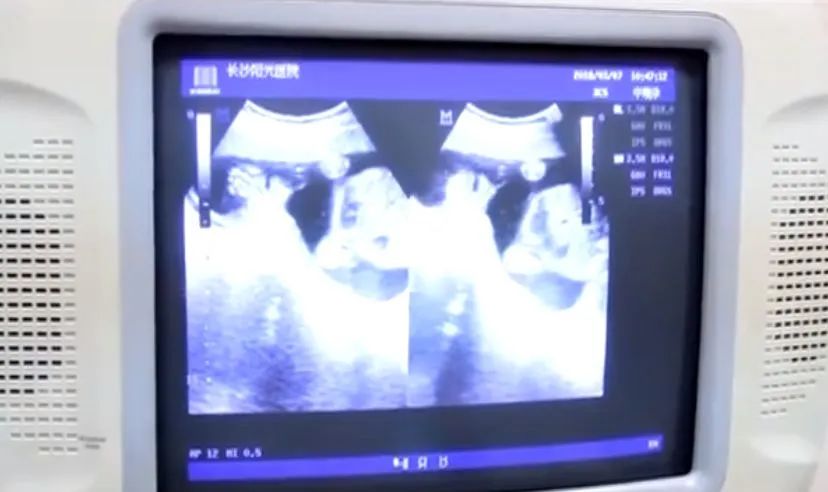

从B超结果来看,这位女士将因此可能失去生育能力。